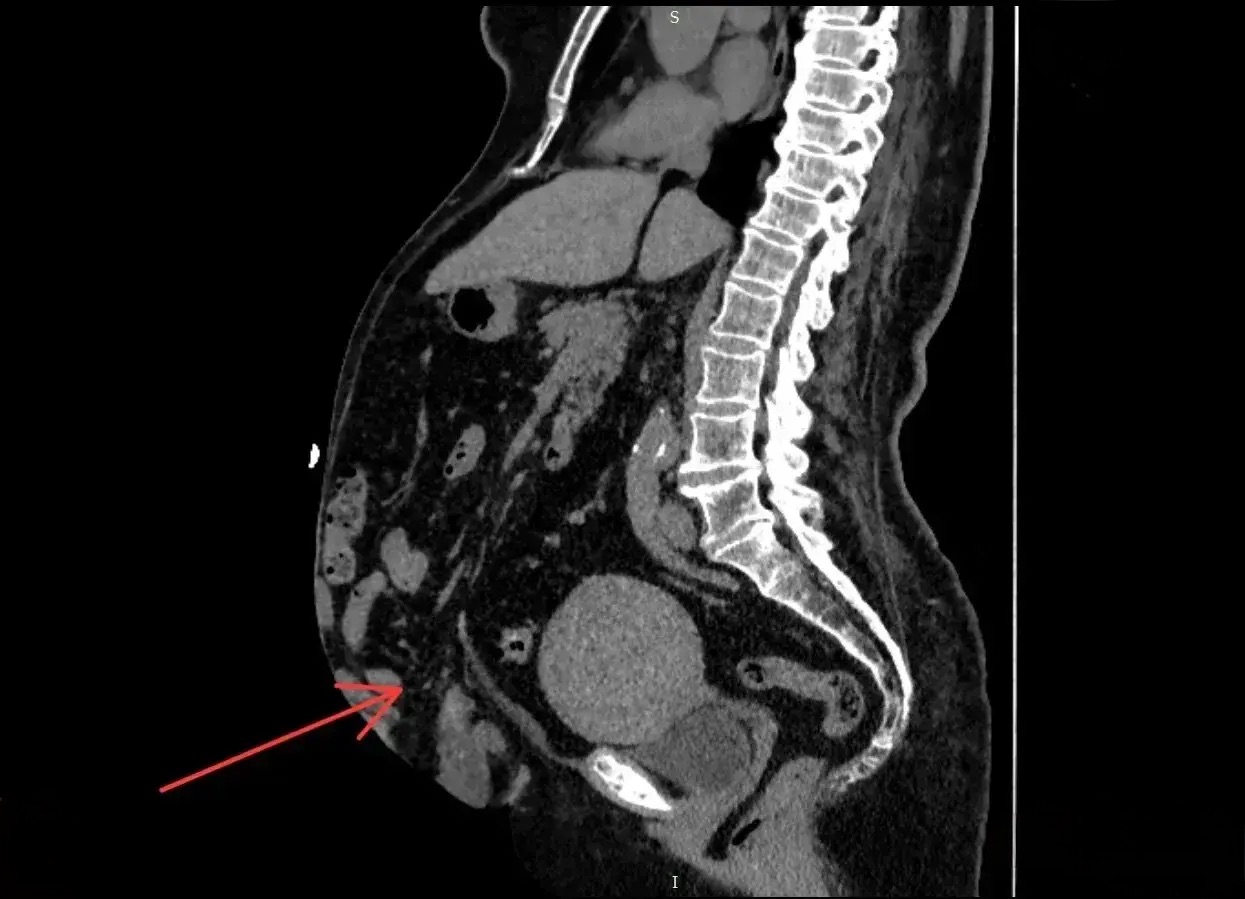

Женщина долго откладывала повторное вмешательство, но когда неприятные ощущения стали невыносимыми, она обратилась в приемный покой Новгородской областной клинической больницы. Компьютерная томография выявила, что грыжа составляет 41% объема брюшной полости — такое состояние называют потерей домена.

Хирурги приняли решение провести ненатяжную пластику с полной реконструкцией брюшной стенки. Такой современный подход позволяет уменьшить риск осложнений и сократить время операции.